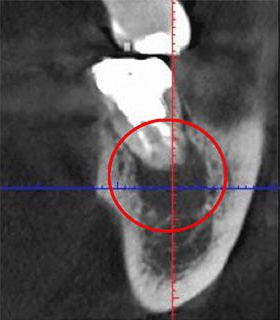

次の画像をご覧ください。これは、CTとレントゲンで同じ患部を撮影した画像です。

左の画像がCT、右がレントゲンで撮影したものです。

左の写真の赤丸で囲んだところは黒い影が映っています。これは「炎症」を示しています。一方、右の写真には黒い影はありません。つまり、レントゲンだけを使って診断すると、この炎症には気付かないということです。放置している間にこの炎症は悪化し、抜歯となってしまうかもしれません。

CTの鮮明な影像によって、正確な診断が可能になります。